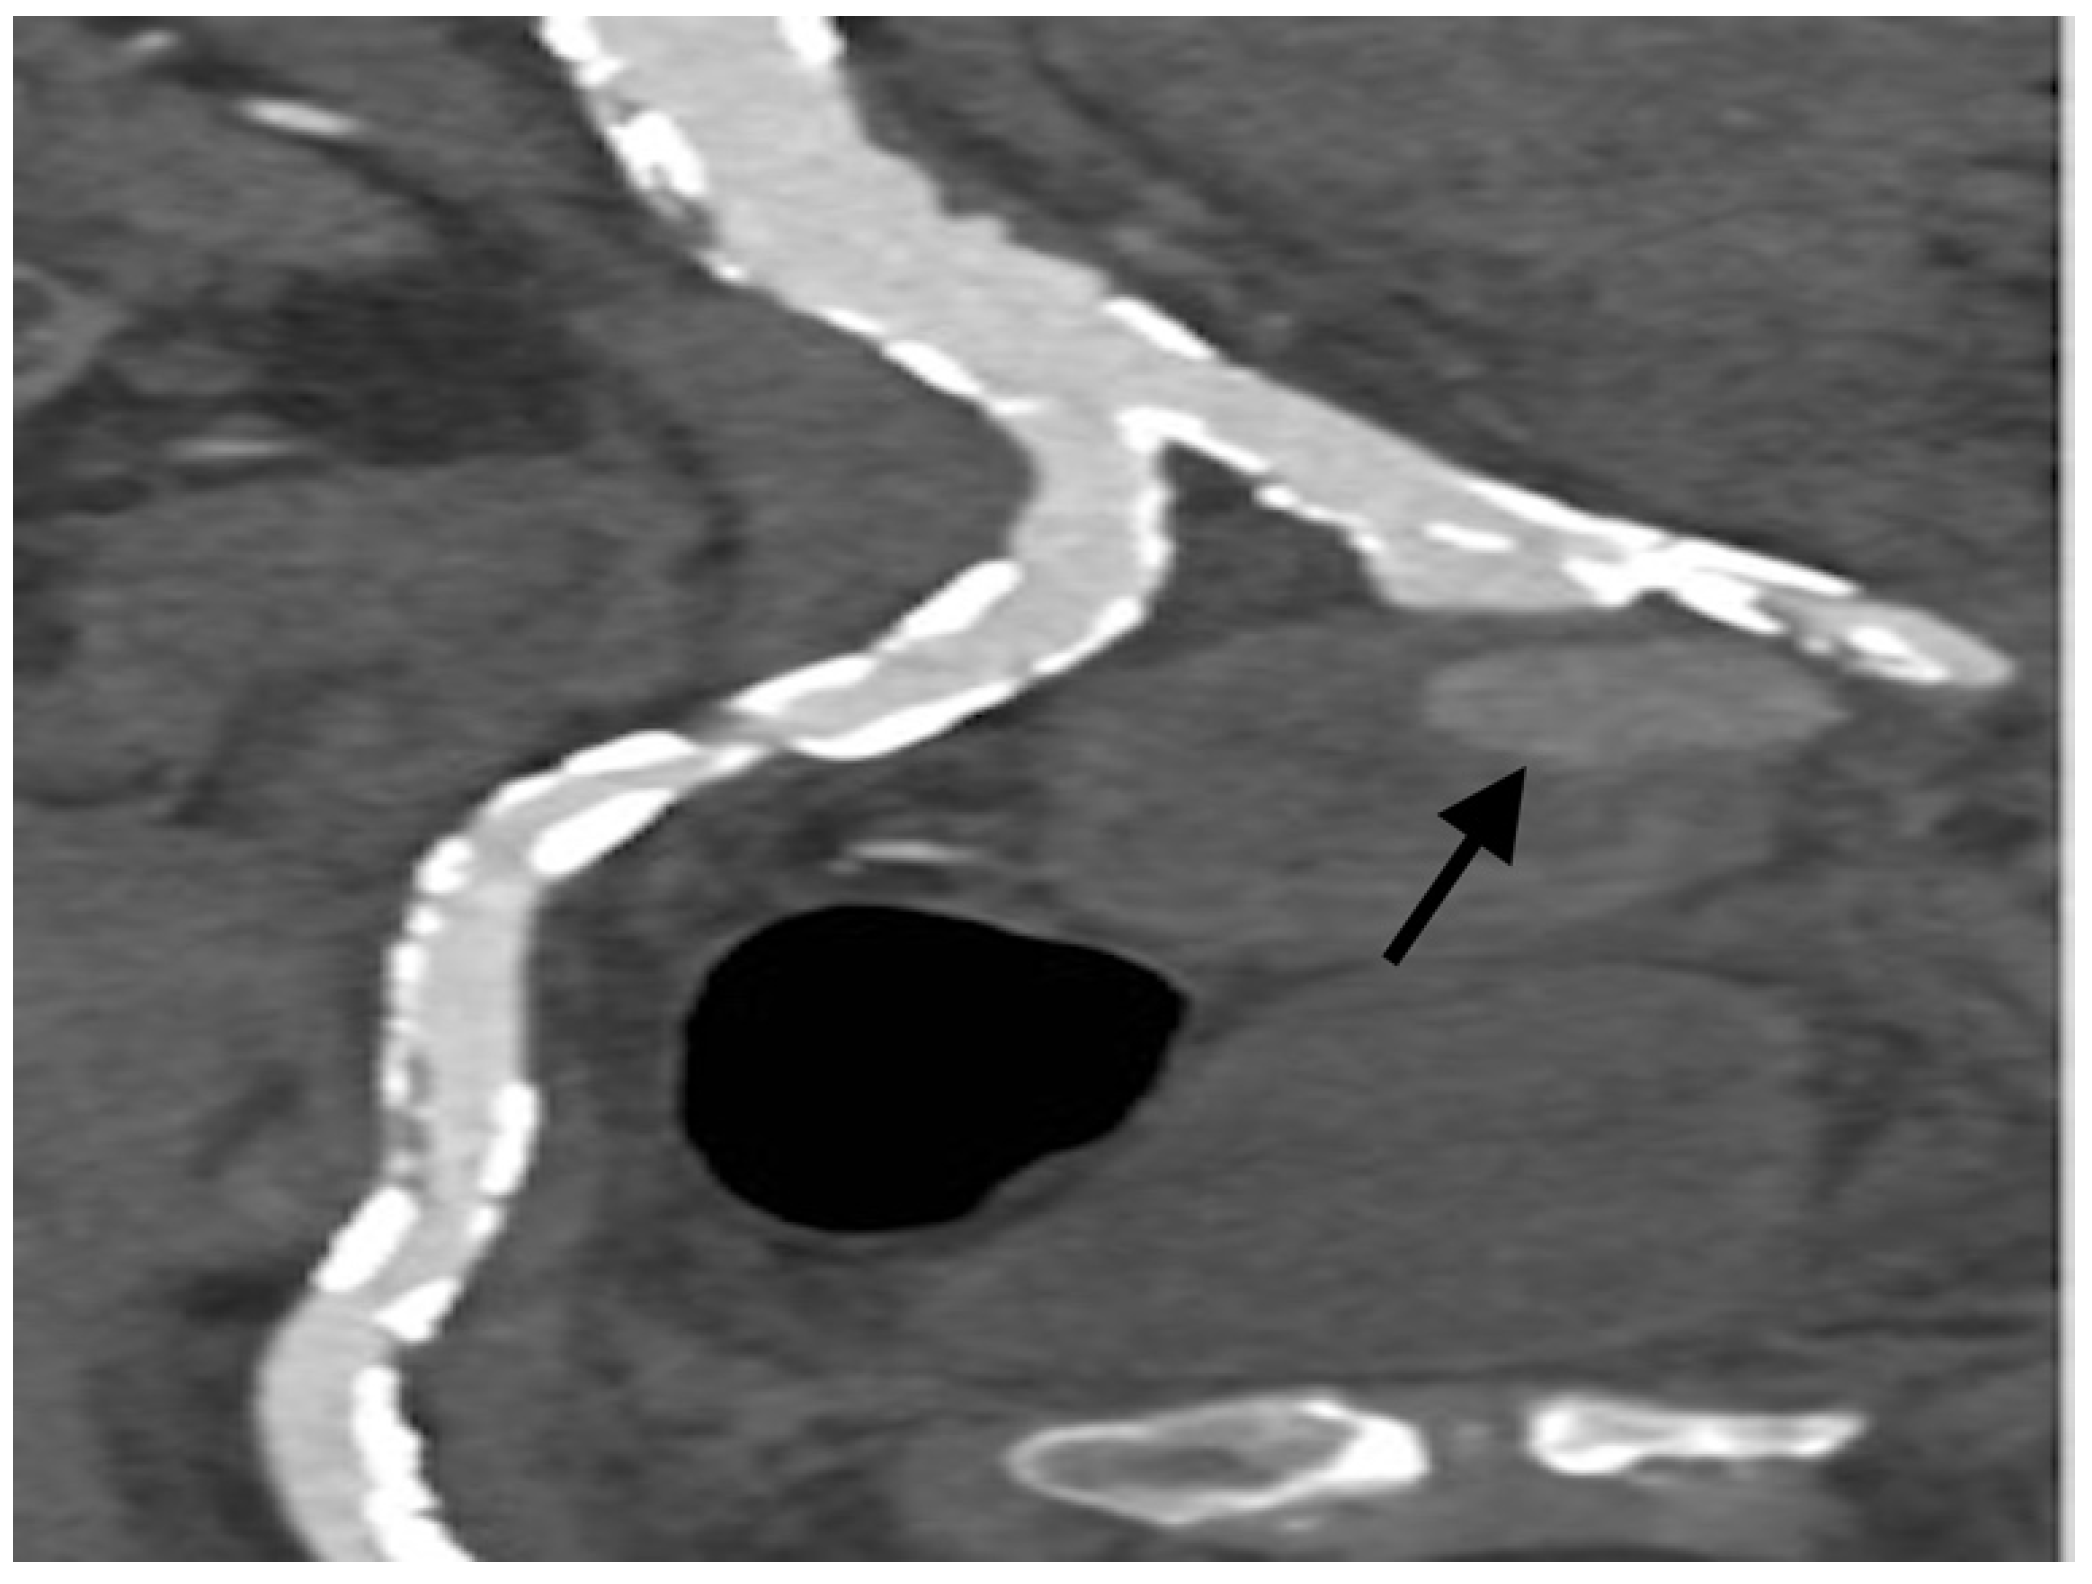

2. Case Presentation